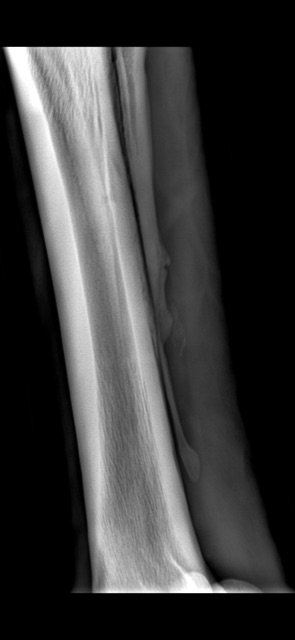

Omg I just realised whatever I just marked goes all the way up the leg 🙈

It does. So this horse started off with a splint bone fracture. At their 4 week xray check up we saw the horizontal crack all the way across the bone too. If that had moved or displaced the horse would be dead. Luckily for the horse we spotted it when we did, wrapped it back up for a few weeks, rehabbed and they raced on for another couple of years. It's a really weird rare one as they rarely crack horizontally without it being fatal. It wasn't seen at he first xray as you don't always see the full extent of the damage for a few days. So it will have been sitting their waiting to show.